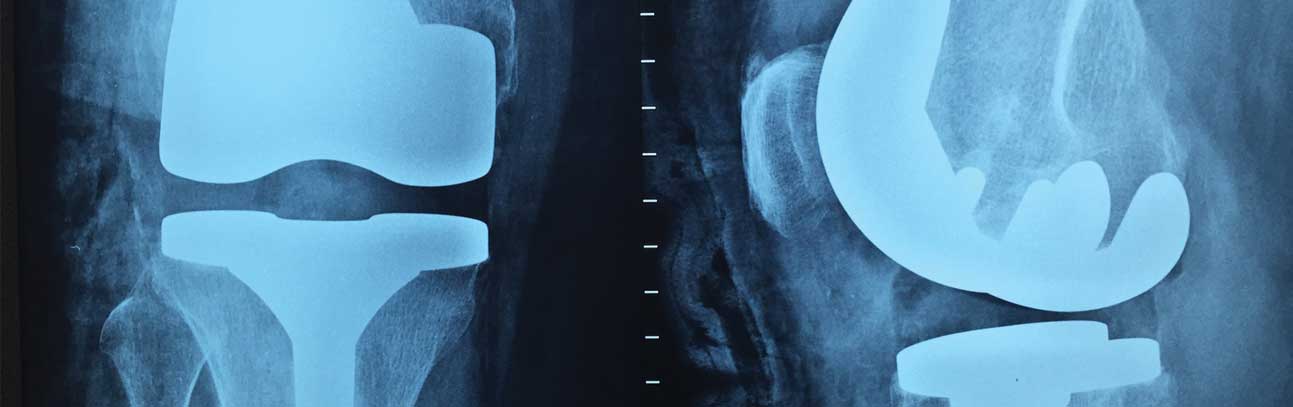

Your Houston-Based Defective Knee Replacement Lawyers

Knee replacement surgery is rather common. But, sadly, knee replacement lawsuits happen just as frequently. The number of patients who require surgery because of defective artificial knees has doubled in the last ten years.

Defective Knee Replacement Devices and Their Expensive, Painful Complications